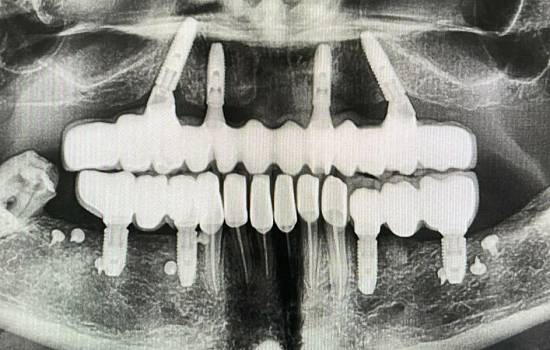

Исследование на рентгене после имплантации зубов

Раздел: Снимки-откровения